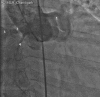

Figure 4

Left main coronary artery arising from the aneurysmal sac. 1, Left main coronary artery; 2, left coronary sinus aneurysm.